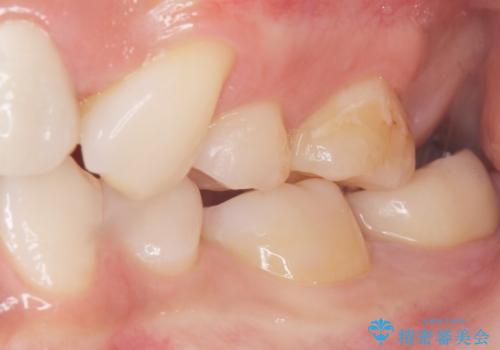

セラミッククラウンの自然な仕上がりと咬み心地にご満足頂けました。

クラウンの種類:オールセラミッククラウン スタンダード